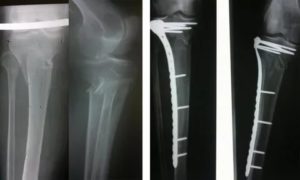

Наиболее часто врачи назначают рентгенологическое обследование и производство снимков. Методика позволяет диагностировать перелом большой и малой берцовой кости. При повреждении нерва показана электронейромиограия.

Если перелом в области мыщелков или оскольчатый показано проведение МРТ. Методика позволяет уточнить вид перелома, особенно если перелом большой берцовой кости без смещения, невидимый на рентгеновском снимке.

При повреждении каждого отдела кости используются свои методики, для которых разработаны соответствующие фиксаторы.

Рассчитаны фиксаторы на пожизненное использование, но примерно через год после постановки при условии консолидации перелома могут быть удалены. При открытом переломе врач может установить внешней фиксатор или аппарат по методике Илизарова.

Если вытяжение не приносит должного результата, то больному назначается оперативное вмешательство, во время которого костные отломки фиксируются с помощью стержней, шурупов, пластин или аппарата Илизарова.

Пластина

В коже делаются отверстия, и к кости с помощью специальных саморезов прикручивается пластина. Данная операция не проводится при переломе голени у детей, потому что во время нее может повредиться надкостница, что негативно скажется на процессе роста кости.